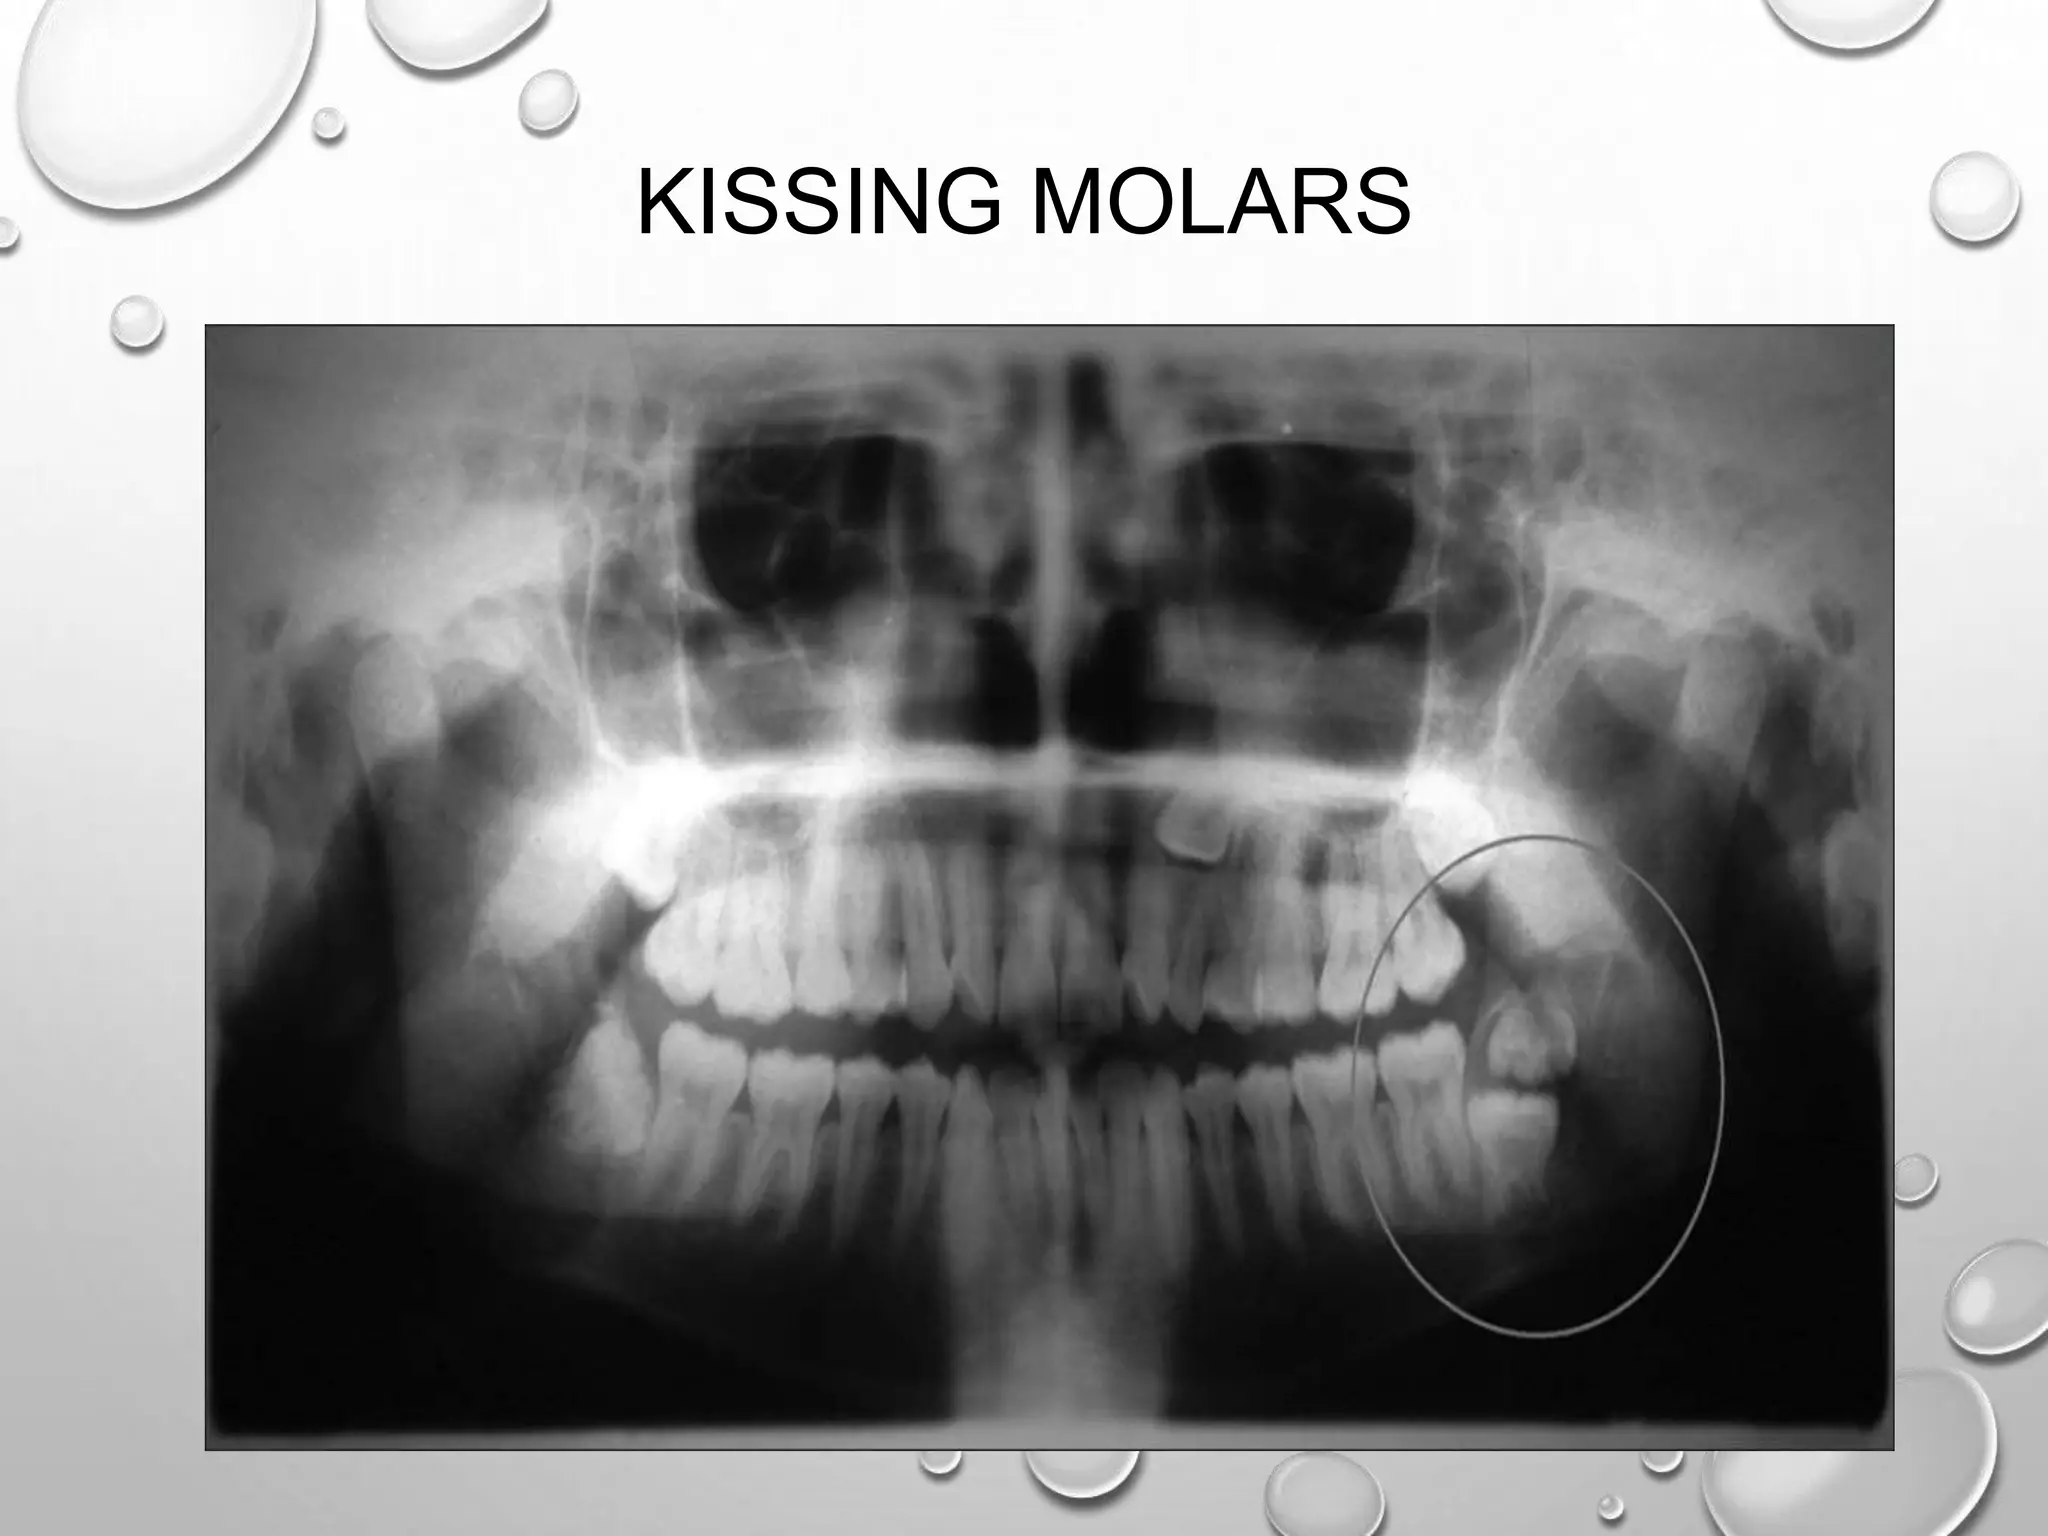

KISSING MOLARS